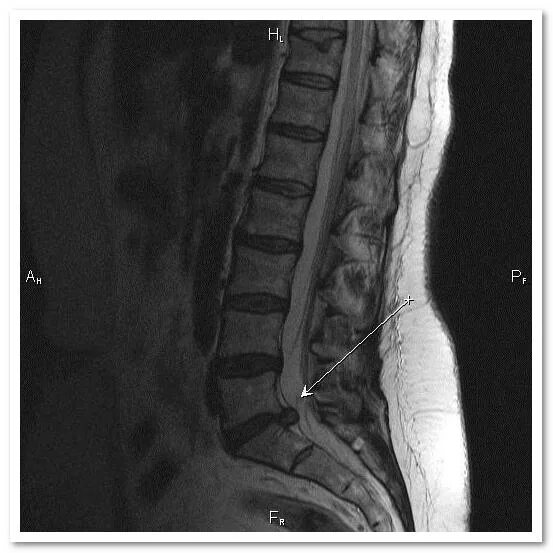

Симптомы позвоночного грыжи поясничного